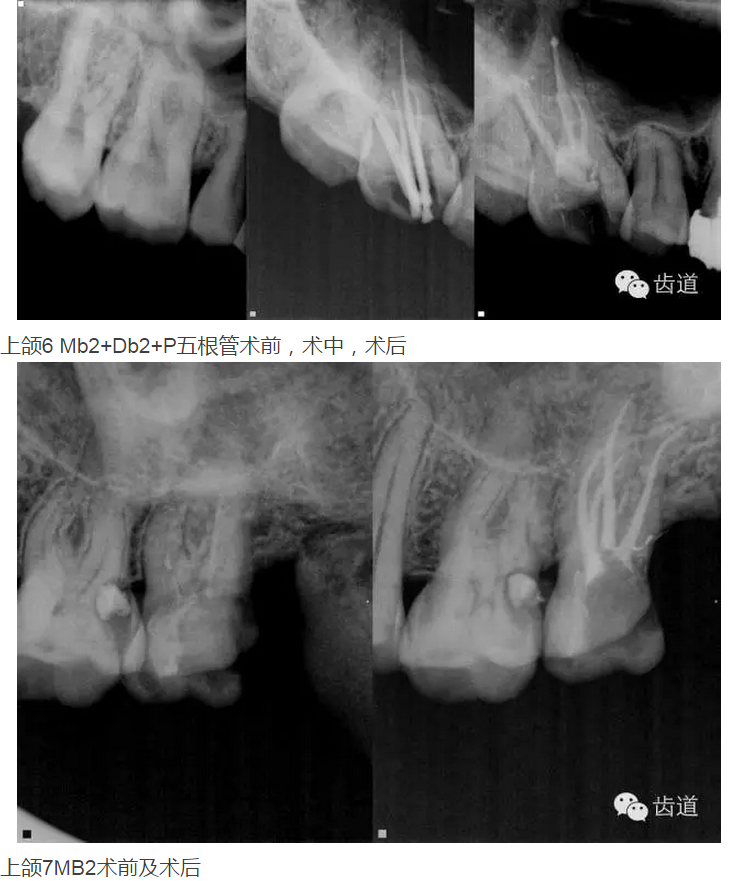

上頜第一磨牙:多為3-4個根管,MB2發(fā)生率約為60%;

上頜第二磨牙:與上頜第一磨牙相似,多為3根管,偶見雙鄂根管;